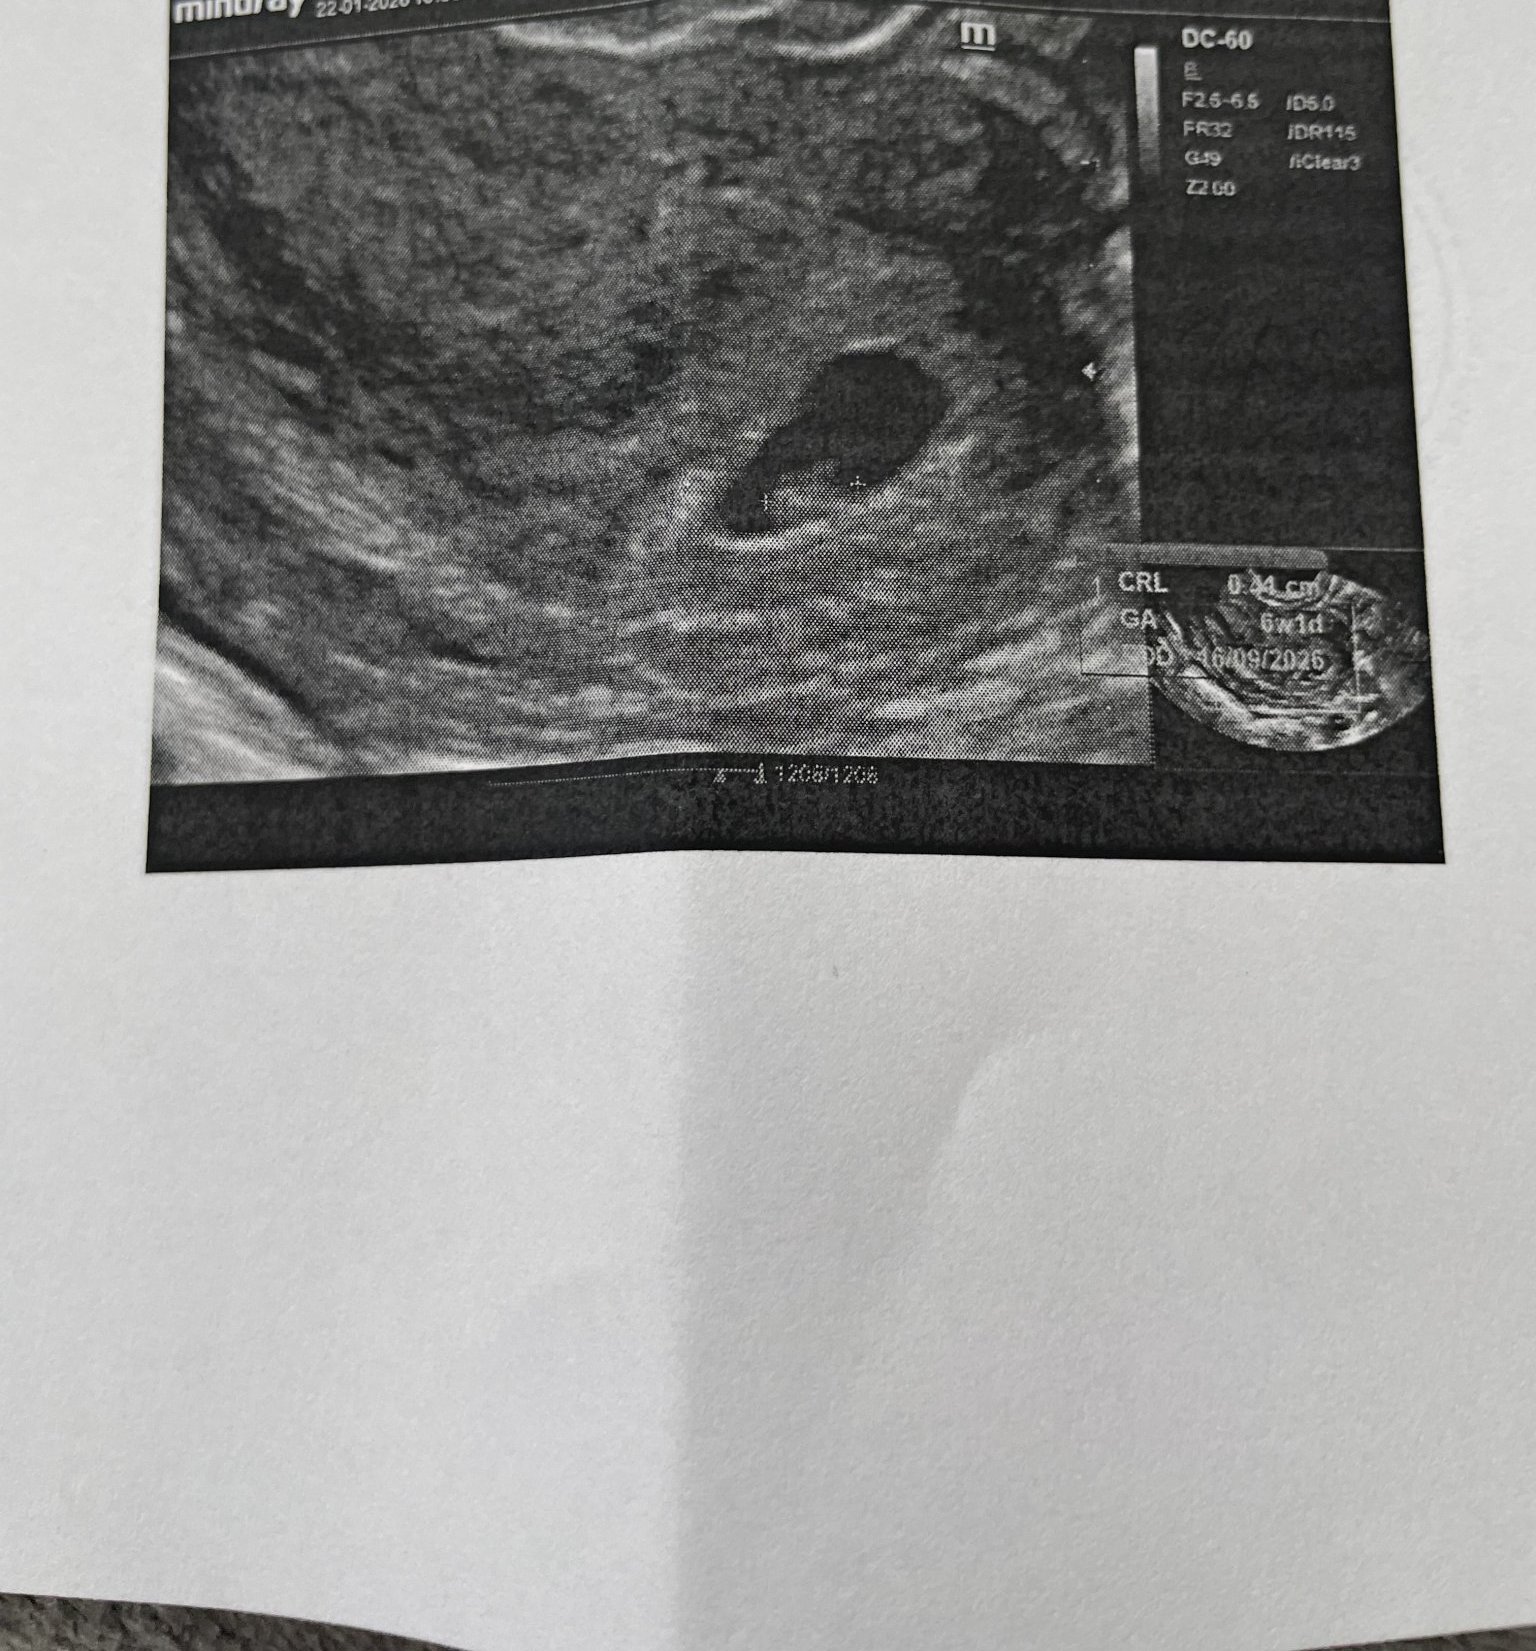

Ето я и снимката изписа ми Келп да пия всичко изглежда наред за 6+1 нали 🫤